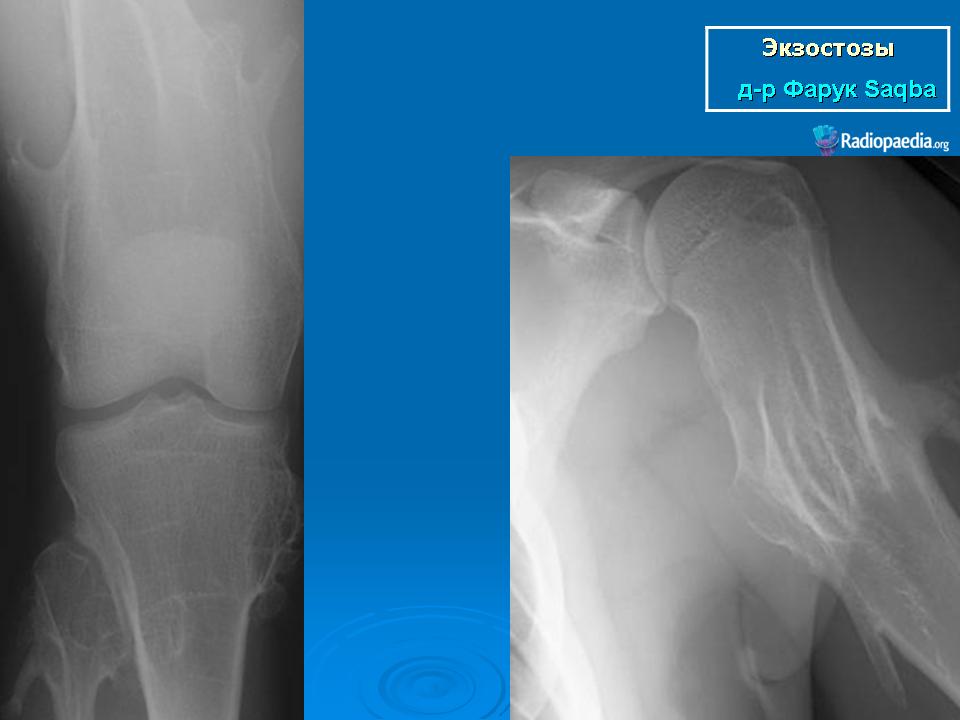

Локализация остеохондромы: частота поражения отдельных костей различна; нижний коней бедренной кости, верхние отделы плечевой и большеберцовой костей поражаются более чем у половины больных. На всем протяжении остеохондрома покрыта надкостницей. Она может быть обнаружена и в других костях, за исключением костей лицевого черепа. Все же поражение костей позвоночника, кистей рук и стоп встречается редко. При рентгенологическом исследовании видна типичная картина узкого или широкого выроста вблизи эпифизарной части пораженной кости. Обычно плотность узла неоднородная, имеются многочисленные плотные участки, соответствующие обызвествленным хрящевым долькам. Хрящевая «шапочка» большей частью не определяется, поскольку хрящ остается необызвествленным. Она может быть выявлена только при магнитно-резонансной томографии.